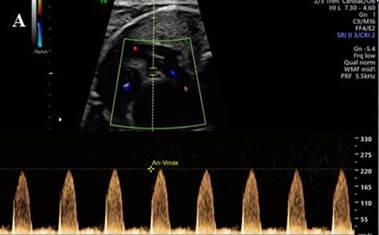

Chest X-ray presents cardiomegaly and pulmonary edema. Mechanical respiratory

assistance is initiated and prostaglandins are administered. Color Doppler

echocardiography shows critical aortic stenosis with severe left ventricular

dysfunction (Figure 1A).

Fig.

1. Doppler echocardiography showing

critical aortic stenosis (A). Angiography through carotid access post

aortic valvuloplasty (B). Angiographic

reconstruction of surgical cerclage in both pulmonary

branches (C).